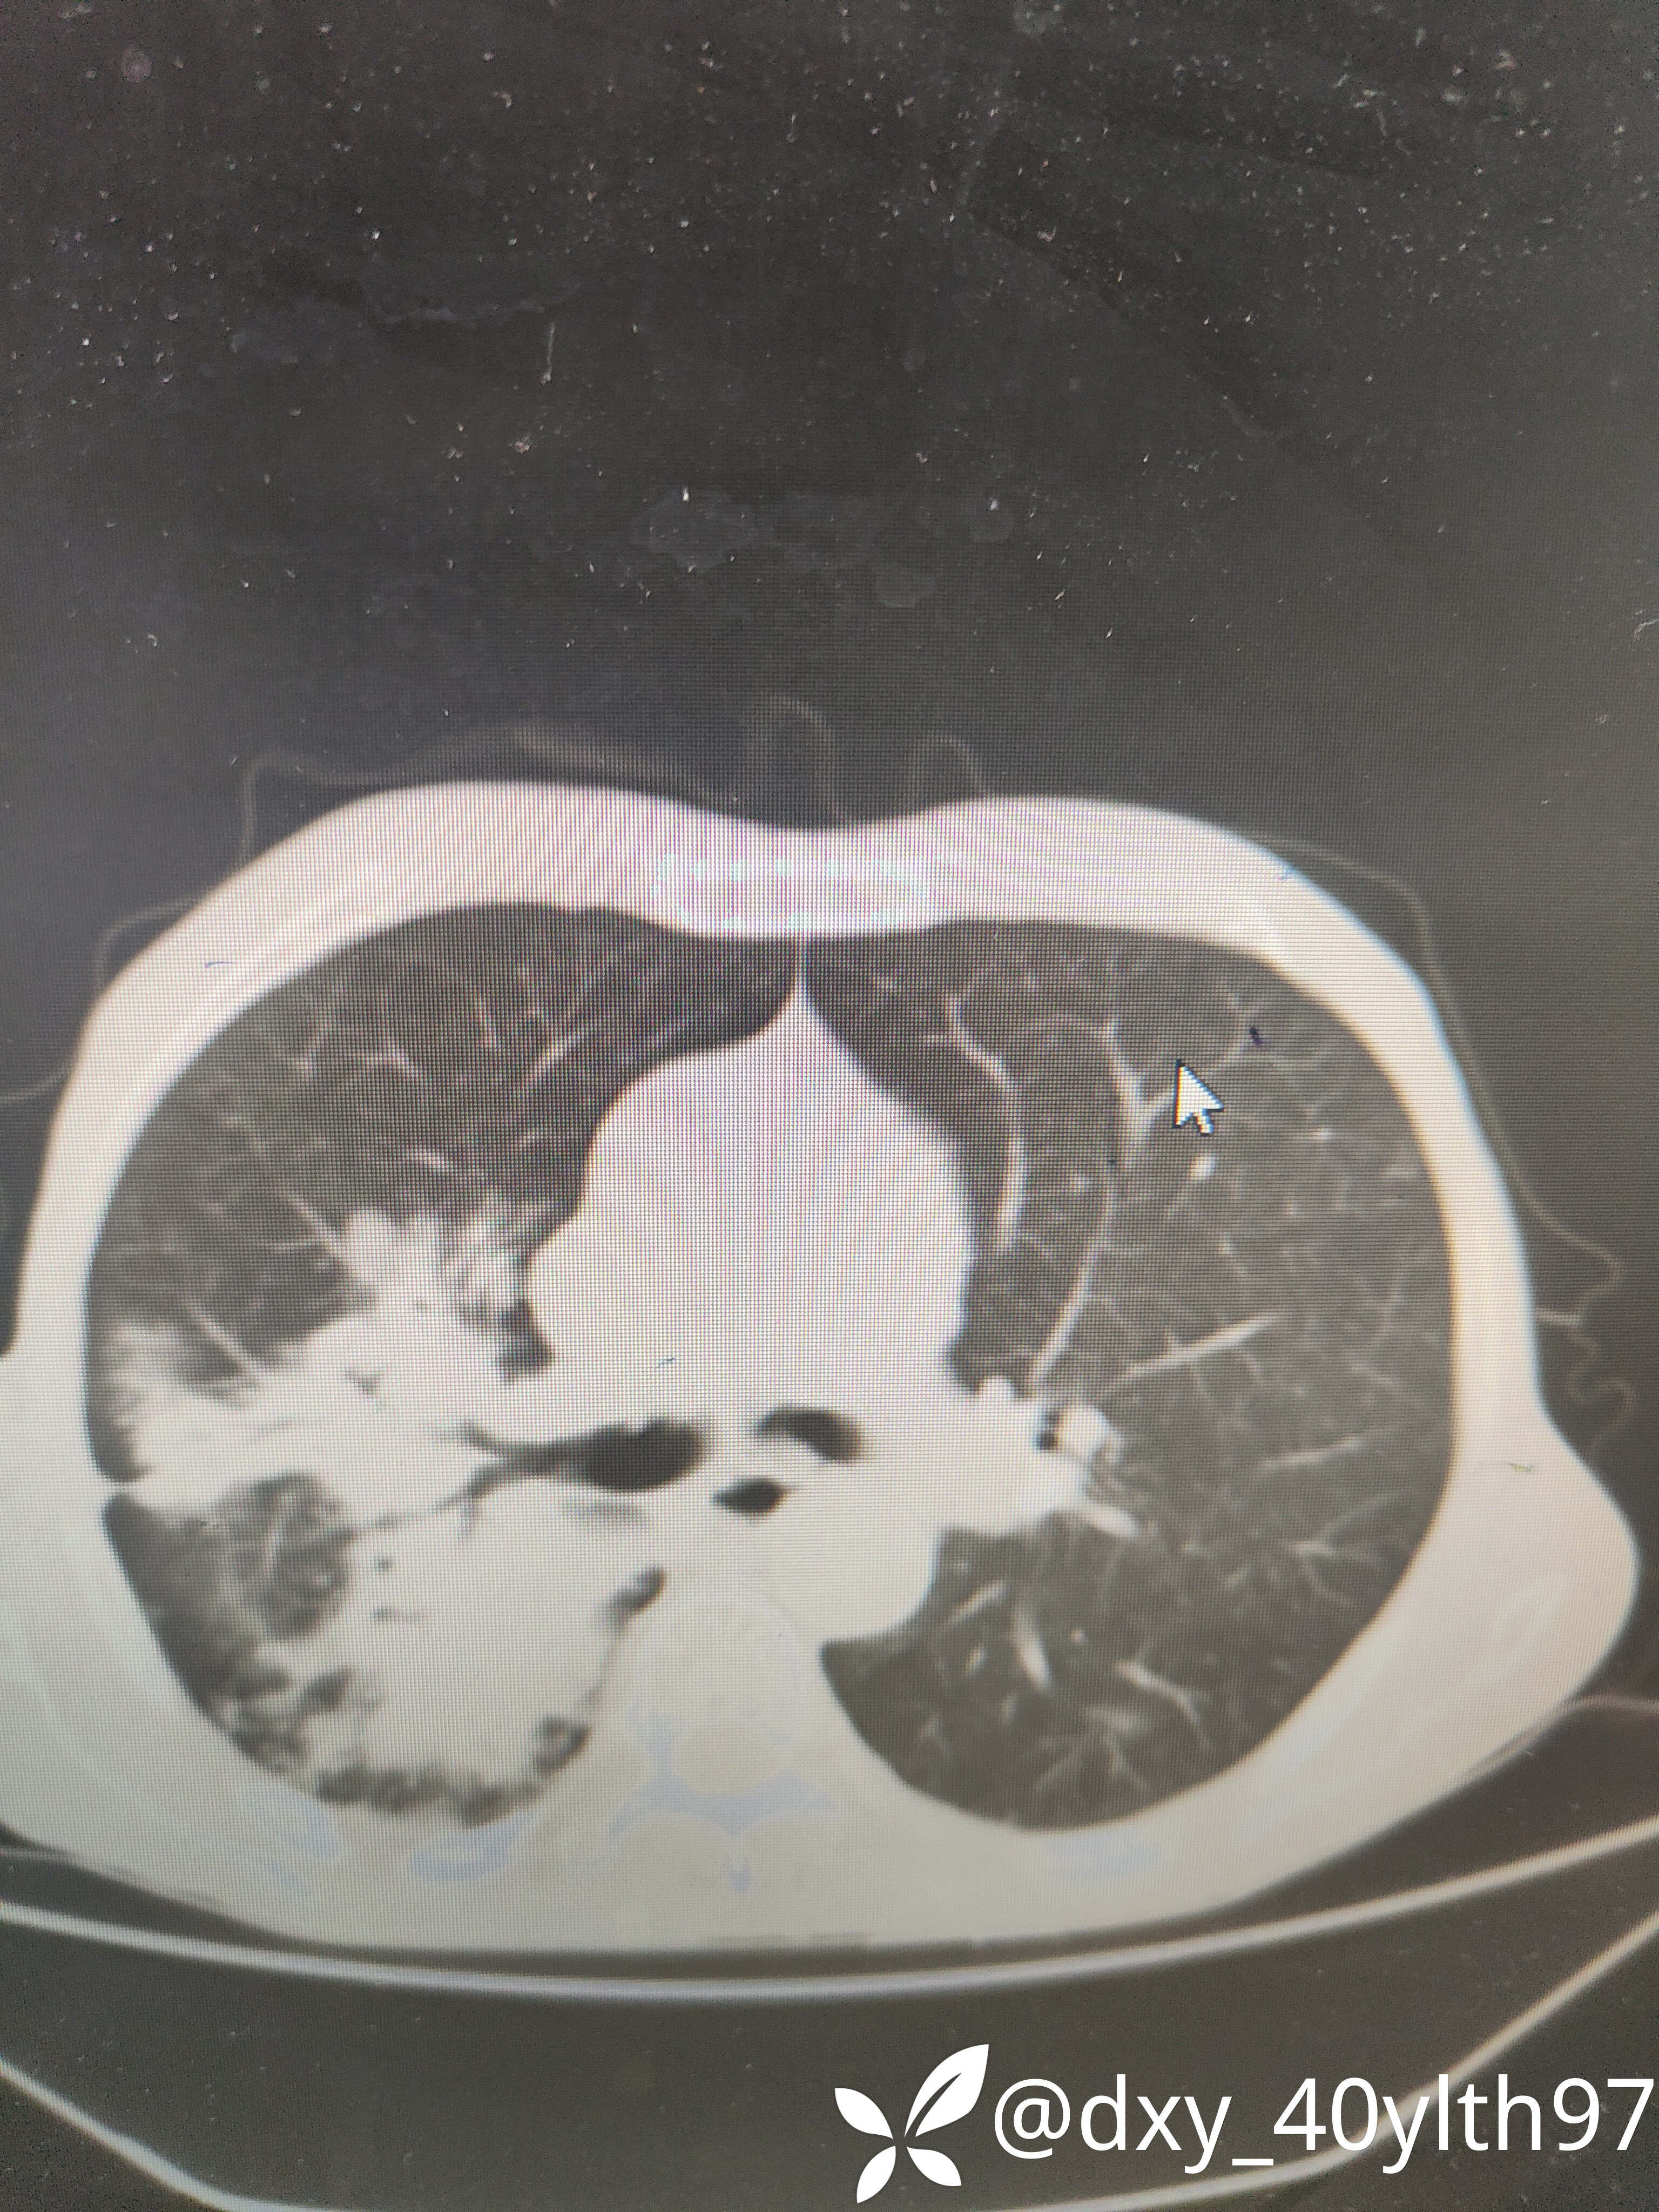

2021年5月首次肺部CT平扫,影像报告提示1.两肺慢性支气管炎、肺气肿、多发肺大疱;2.右肺中下叶多发感染性病变、结节、右肺门增大,建议治疗后复查或进一步检查排查右肺门区肿瘤性病变;3.左肺上段舌叶散在炎性病变

2021年8月因2型糖尿病入院复查肺部CT平扫,影像报告提示:胸部CT复查:1.右肺中下叶感染范围较前相仿、密度增高;2.右肺门区病变较前有所增大;3.右肺外基底段结节较前吸收。

2023年8月肺部CT平扫影像结果提示:1.右肺上叶密度增高影较前显著增大,建议进一步检查;2.两肺多发斑片结节灶较前增多,部分增大。

肺部增强CT影像学提示:右肺内大片不规则影轻度强化,肿瘤可能。